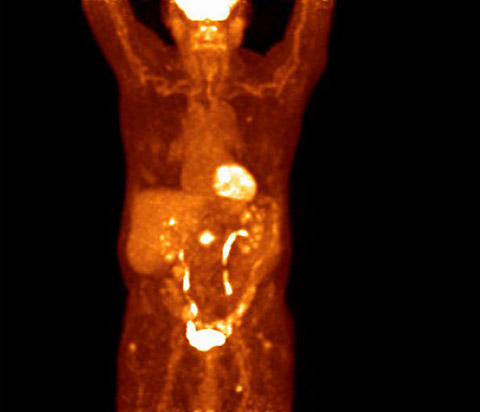

Avec une sensibilité environ deux fois plus élevée qu’un système analogique*, la caméra TEP/TDM Vereos permet une meilleure détection des lésions grâce à une résolution et un contraste améliorés. Constatez la différence de qualité d’image à partir de cette image de thorax. *GEMINI TF 16

Examen d’imagerie TEP analogique*

En convertissant la lumière directement en un signal numérique avec un bruit pratiquement nul, la technologie de comptage de photons numérique offre un meilleur rapport signal-bruit, augmentant ainsi la sensibilité. Associée à une résolution temporelle rapide, la sensibilité accrue améliore le contraste de l’image, permettant une détection optimisée des lésions.